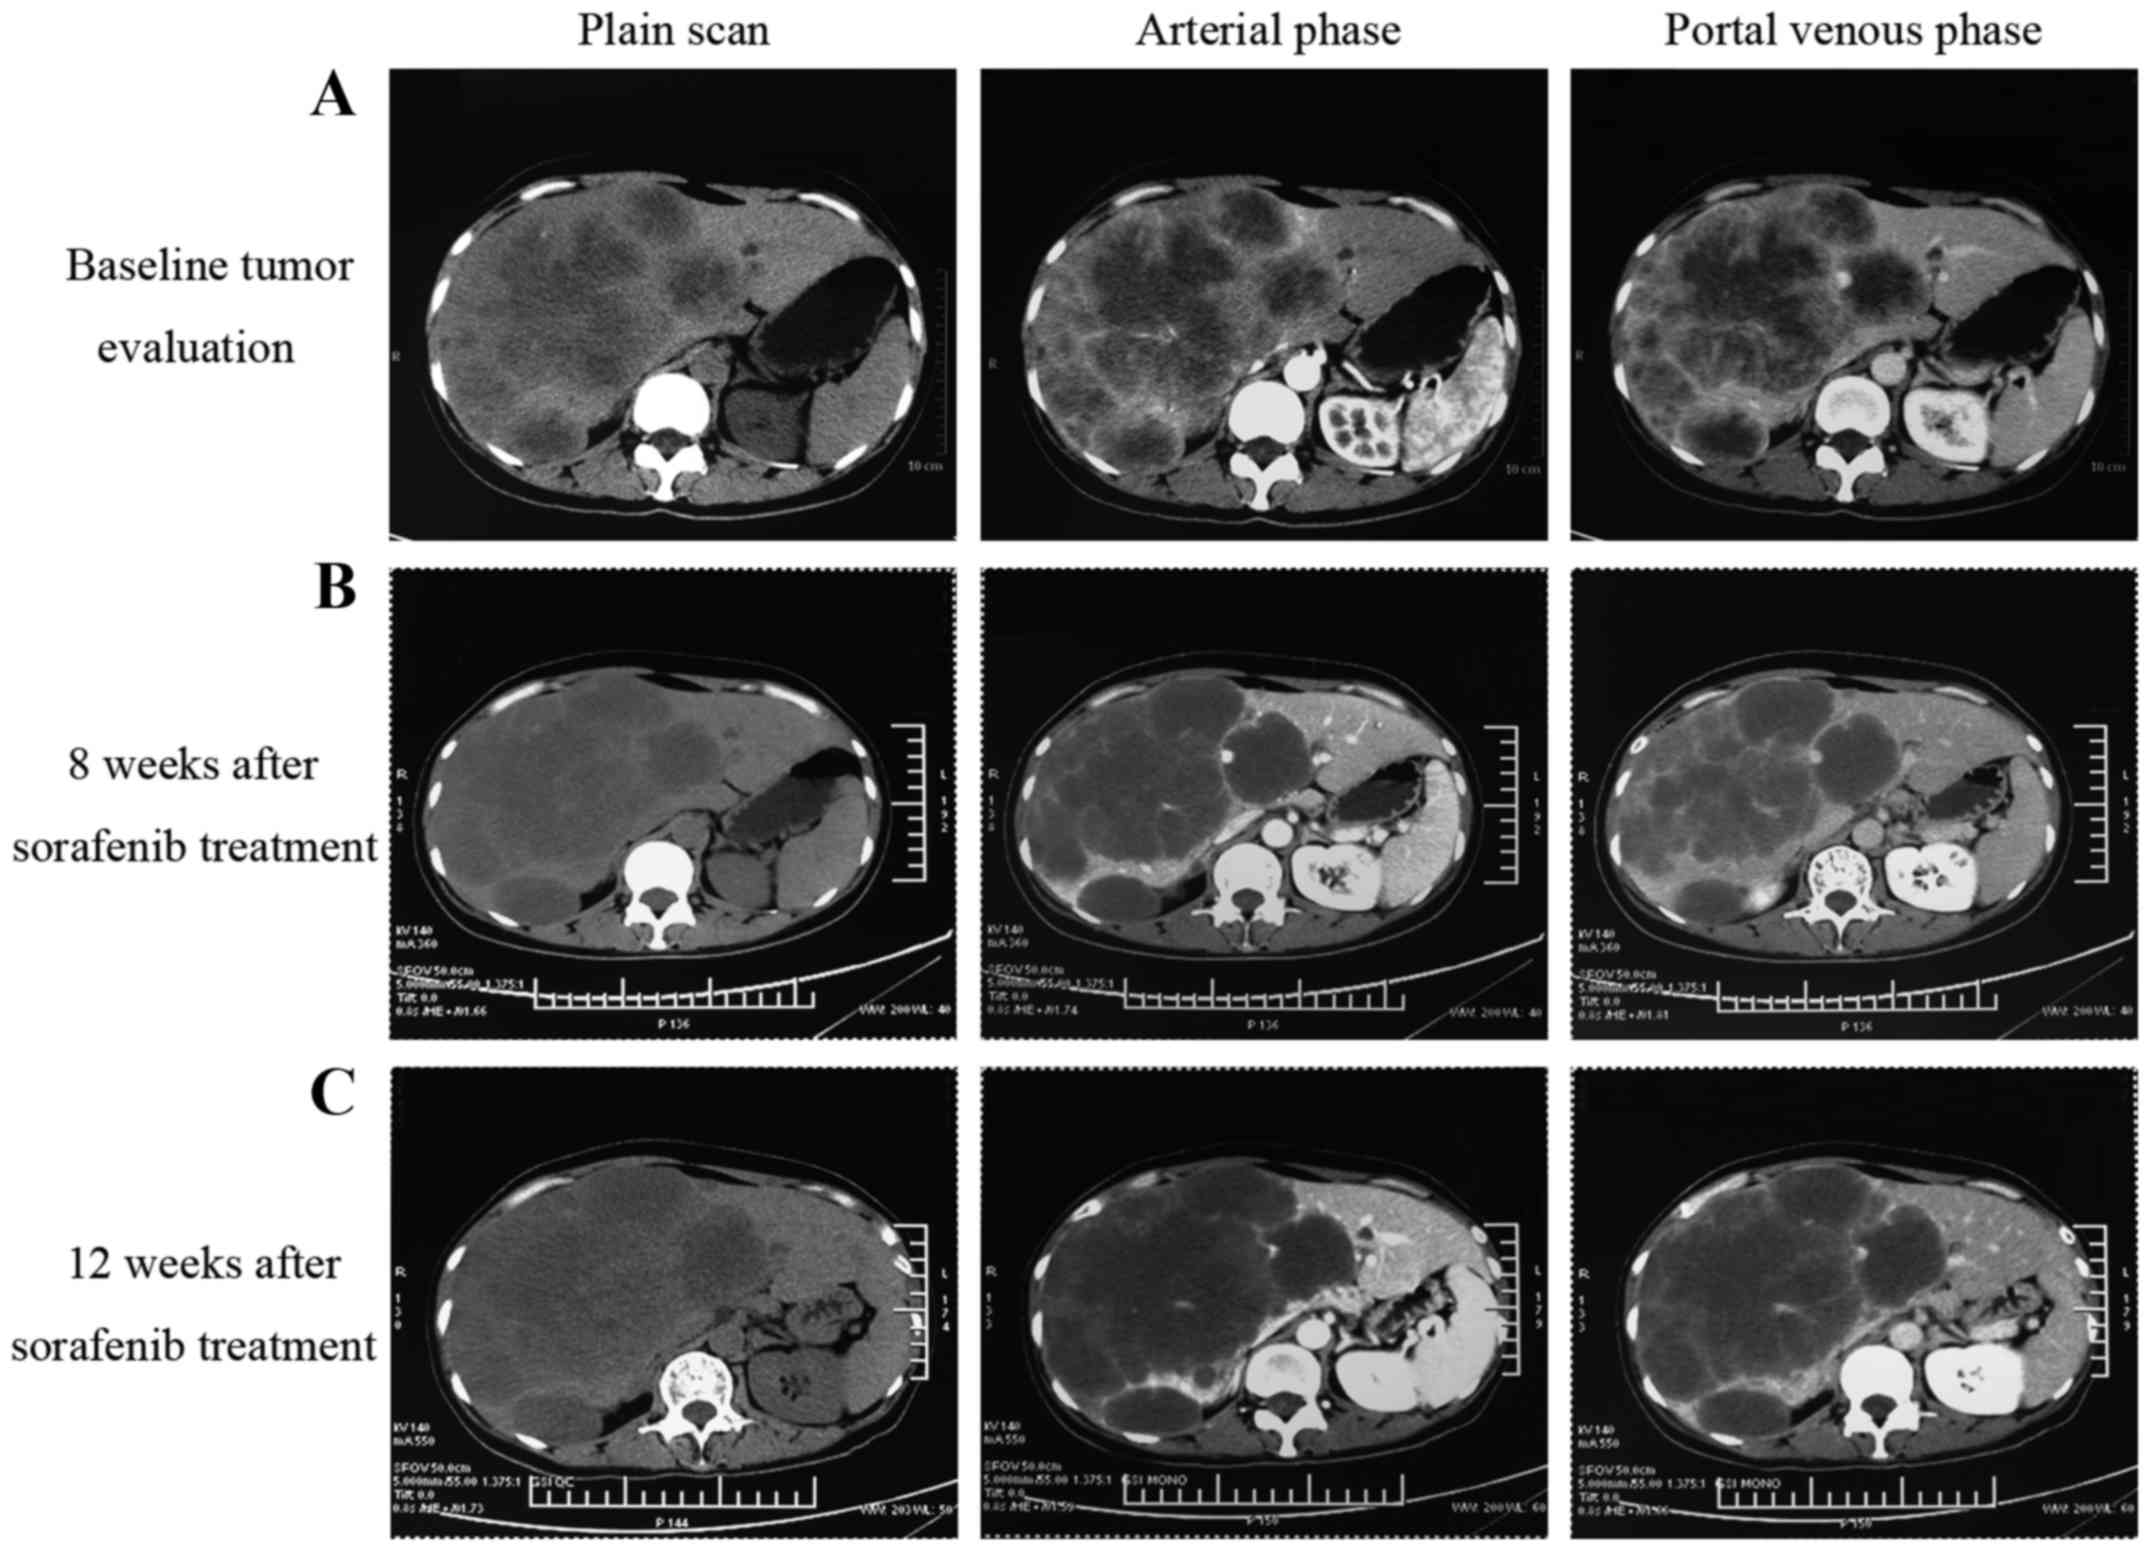

Cholangiocarcinoma (bile duct cancer) - Mayo Clinic Intrahepatic cholangiocarcinoma (ICC) is a subtype of a family of aggressive cholangiocarcinomas, tumors that arise from cholangiocytes of the biliary tree. This condition occurs slightly more often in males than females and usually affects people who are between 50-years old. Intrahepatic cholangiocarcinoma has a variety of treatments that can be used alone or with other treatments to produce the best outcome for your specific cancer. It can sometimes be confused with cancer that starts in the liver cells, which is called hepatocellular carcinoma.